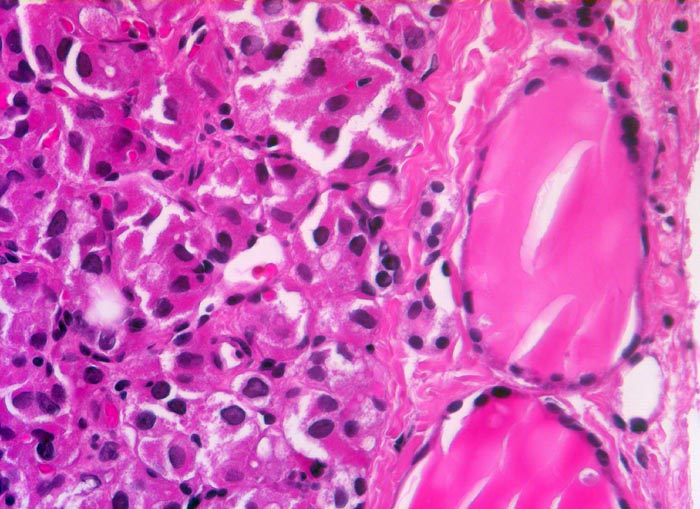

Rechts im Bild zwei normale Follikel mit flachem Epithel und reichlich Kolloid. Die neoplastischen Follikel links im Bild sind sehr klein und enthalten kaum Kolloid. Die Tumorzellen haben vergrösserte polygonale Kerne und reichlich Zytoplasma.

Seit zirka 10 Jahren ist beim Patienten eine Struma bekannt. Jetzt sucht er den Hausarzt auf, weil er den Eindruck hat, die Schilddrüse sei grösser geworden. In der Ultraschall-Untersuchung wird ein Knoten im rechten Schilddrüsenlappen festgestellt, der relativ scharf vom angrenzenden Gewebe abgesetzt ist. Die Feinnadelpunktion ergibt eine follikuläre Neoplasie; eine Unterscheidung zwischen einem follikulären Adenom und einem follikulären Karzinom ist zytologisch jedoch nicht möglich. Es wird eine Hemithyreoidektomie durchgeführt und nach der Diagnosestellung eines follikulären Karzinoms eine Resthyreoidektomie angeschlossen.